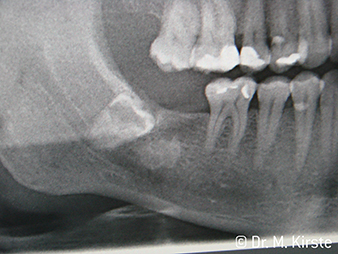

The dental handpieces WS-91 and WS-91 L G combine the advantages of surgical straight and contra-angle handpieces for the first time ever (Fig. 1). The extended angle between the shank and bur axis allows good access to the tooth row both buccally and occlusally (Fig. 4). Displaced teeth can be comfortably sectioned (Fig. 6 and 7). The dentist also has a significantly better view of the surgical site than with the instruments previously available. Dr. Mario Kirste from Frankfurt/Oder had this to say, “If I turn the contra-angle handpiece head slightly, I can work particularly quickly and safely in the retromolar region. The instrument has the potential to reconcile the contrasting positions taken up by the users of straight and contra-angle handpieces.” (Fig. 2-5)